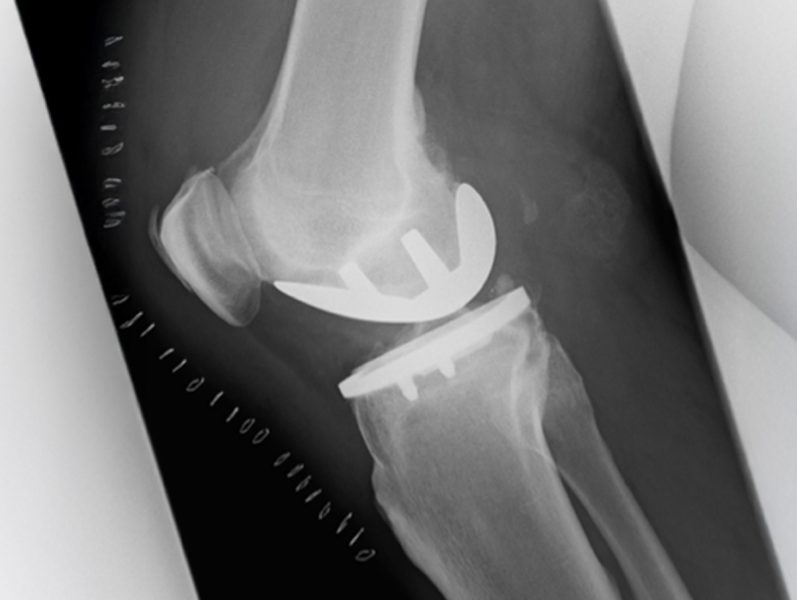

In unserer Abteilung werden primäre und Revisionsendoprothesen an Hüft –, Knie – und Schultergelenken durchgeführt.